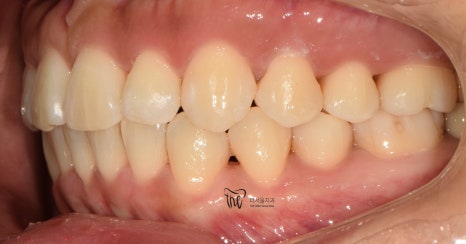

측면에서 봤을 땐, 앞니들의 뻐드러짐과

불규칙한 치열을 동시에 관찰을 할 수 있습니다.